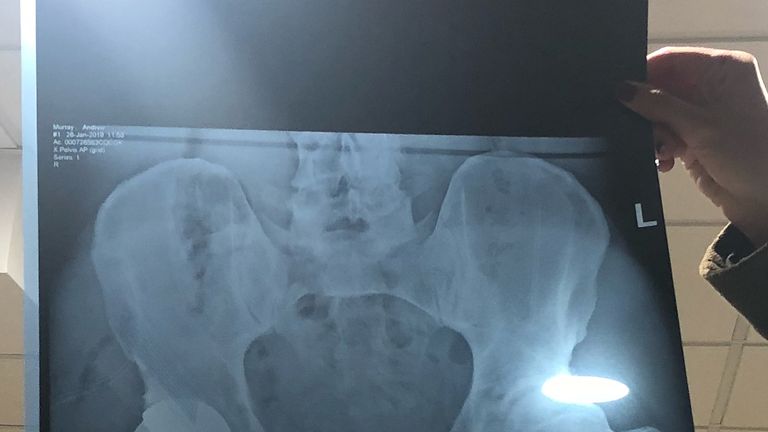

The x-ray show's Andy Murray's new metal hip (Credit @andymurray Instagram)

Image: The X-ray shows Murray's new metal hip (via @andymurray on Instagram)

"I now have a metal hip as you can see in the 2nd photo and I look like I've got a bit of a gut in photo 1."